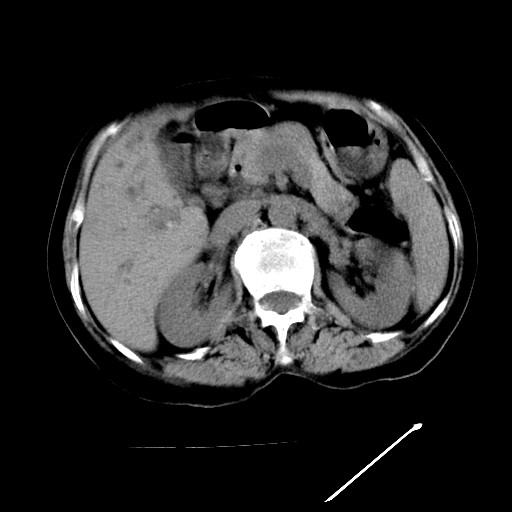

以下是引用随光逐影在2009-4-7 8:21:00的发言:[br]肝内外胆管多发性结石并肝内外胆管扩张;胆系感染。